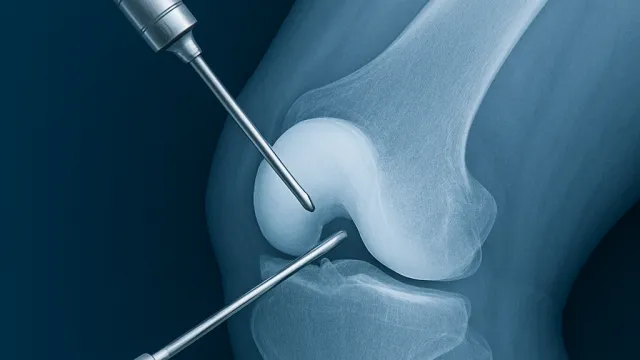

Devamını OkuArtroskopik cerrahi, halk arasında “kapalı eklem ameliyatı” olarak bilinir. Küçük kesilerden ekleme yerleştirilen kamera ve özel aletler sayesinde ekl...